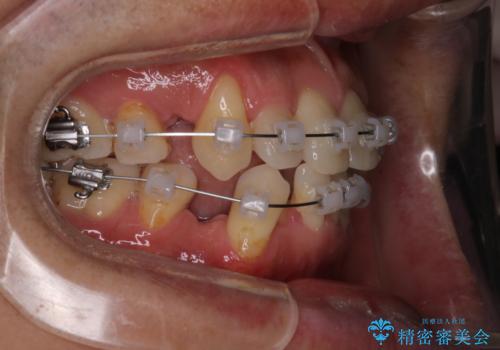

- 治療計画

叢生量が大きいため、上下顎両側4番を抜歯しました。矯正治療による歯肉退縮の著しい悪化もなく、主訴であるガタつきも改善できました。